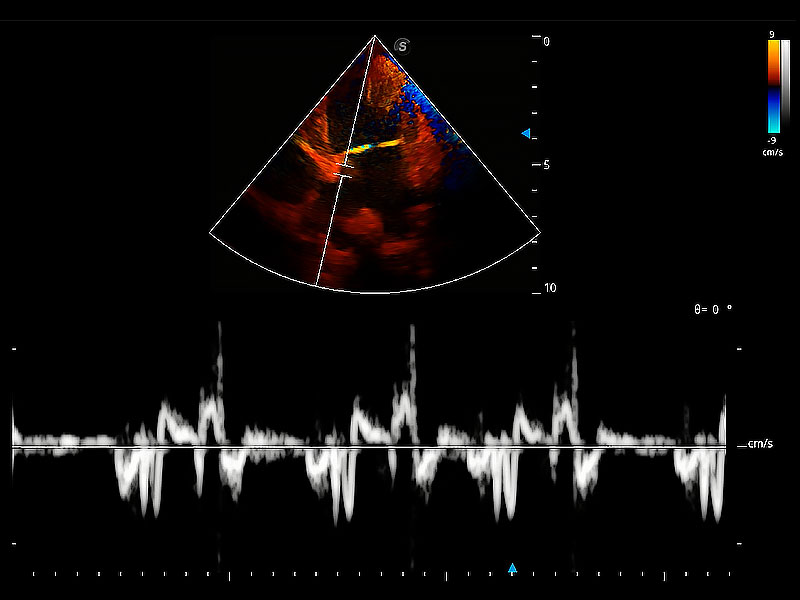

實時用顏色表示心肌組織運動,觀察和定量組織的運動情況,對快速檢測與評估心肌的灌注和活性、電傳導(dǎo)及心肌收縮和舒張功能等均能提供重要的診斷信息。

ProPet 80 配備了豐富的心臟探頭群、先進的成像技術(shù)和專業(yè)的心臟測量工具,可幫助動物醫(yī)生為不同體型和生理結(jié)構(gòu)的動物提供心臟和心肌功能的全面評估。